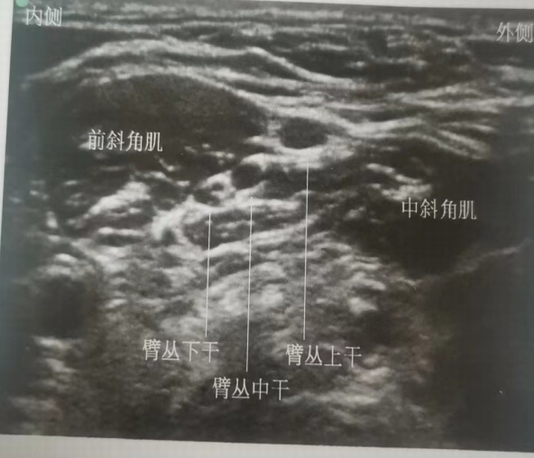

超声引导下臂丛神经阻滞术